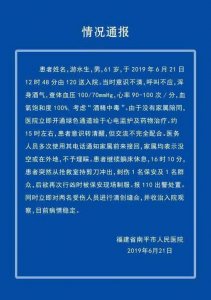

一男子酒精中毒入院治疗刺伤2人 医院报110出警处置 据福建省南平市人民医院通报,6月21日中午,一名61岁男子酒精中毒后入院接受治疗,医务人员多次电话通知家属,家属不予理睬。...